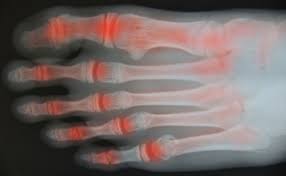

류마티스 관절염은 조기 진단이 특히 중요하므로, 붓기·열감·통증이 계속되면 X-ray·초음파·혈액검사를 시행하는 것이 좋습니다.